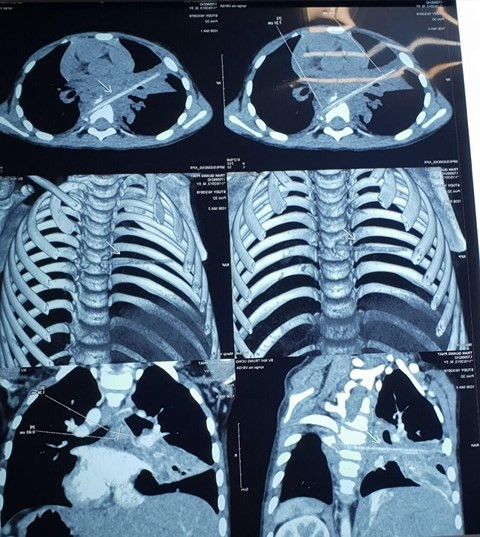

Tháng 1/2018, trong lúc chơi đùa với bạn, bé trai Nguyễn V.M. (5 tuổi, Thái Bình) bị bạn chọc que nứa (loại dùng để xiên thịt nướng) vào vùng ngực bên phải. Sau va chạm, bé M chỉ bị rớm chút máu ở da vùng nách phải. Tuy nhiên, kể từ đó, bé M. liên tục phải đi bệnh viện để điều trị viêm phổi. Tháng 10 năm 2018, khi đến khám tại Bệnh viện Nhi Trung ương, bé được các bác sĩ phát hiện trong cơ thể có một dị vật dài nhọn ở nhu mô phổi thùy bên phải. Đây cũng chính là thủ phạm khiến cháu M. mắc viêm phổi tái diễn.

Ngày 3/10 thấy con trai 5 tuổi bắt đầu có biểu hiện bệnh giống như 2 lần trước, gia đình đã chuyển cháu lên Bệnh viện Nhi Trung ương. Khi chỉ định bệnh nhi chụp cắt lớp vi tính 128 dãy, các bác sĩ nhận thấy trên phim chụp có hình ảnh điểm vôi hóa cột sống và hình ảnh viêm phổi thùy bên phải nhưng không rõ có dị vật vì dị vật không cản quang.

Hình ảnh chụp vi tính cắt lớp sau đó cho thấy bệnh nhi có một dị vật dài nhọn kích thước 72x4mm tại vị trí nhu mô thùy phổi ở thùy giữa phổi phải. Dị vật này đi từ trước ra sau, xuyên qua khe giữa 2 thân đốt sống 6, 7 và làm vỡ thân đốt sống. Khi nằm lại trong cơ thể, dị vật gây phản ứng thâm nhiễm viêm trung thất sau quanh đốt sống 6,7. Đây cũng chính là nguyên nhân khiến cháu M phải vào viện vì viêm phổi trong suốt 8 tháng.

Sau khi phát hiện dị vật trong cơ thể bệnh nhi, các bác sĩ đã tiến hành hội chẩn và chỉ định phẫu thuật cho cháu. Ca phẫu thuật đã lấy ra dị vật là một thanh nứa sắc nhọn dài 9 cm. Sau phẫu thuật, cháu bé được chăm sóc tại khoa Ngoại, Bệnh viện Nhi Trung ương. Với tình trạng sức khỏe ổn định, ngày 12/10 cháu M đã được ra viện.